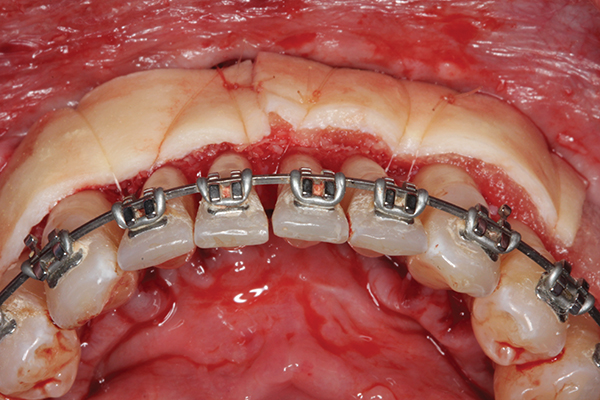

Fig 3. Corticotomy cuts performed.

Figure 3